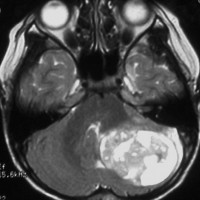

- 境界がはっきりした腫瘍です,くりんとしています

- ガドリニウム造影剤で白く映ります(増強される)

- でも,ガドリニウム造影剤が入らなくて白く映らないものもあります

- 周囲の小脳が腫れることが多いです(脳浮腫)

典型的な小脳虫部(小脳の真ん中)の髄芽腫です。横の方,ルシュカ孔へ伸びていないので上衣腫と区別できます。ガドリニウムという造影剤で白く写っています。

この例は,小脳半球にできたものです。のう胞(水たまり)を形成しています。髄芽腫の大きな特徴は,造影剤を入れないCT(左側)で腫瘍が少し白く見えることです(灰白質より高密度といいます)。細胞密度が高いので高密度になります。この例はclassic medulloblastomaですが,MIB-1は45%に達するもので,急激な腫瘍発育を示します。

単純CTでは,腫瘍は比較的境界明瞭で石灰化も高頻度に認められます。充実性腫瘍であることが多いのですが,のう胞あるいは壊死形成も見られます。細胞密度が高い腫瘍であるのでCT等吸収域もしくは高吸収域として描出され,造影剤では均一に強く増強されます。MRIでは,T1強調画像で低信号域として描出され,T2強調画像で等信号から高信号を呈すします。ガドリニウム増強効果は症例により様々であり,強い均一な増強効果を示す例から,ほとんど増強されない症例まであります。髄液播種の頻度が高いので,全脳脊髄にわたるMRI検査が必須です。また,MRIで髄腔転移が認められなくとも髄液細胞診で陽性となることがあるので,もしできれば腰椎穿刺あるいは脳室内髄液によって細胞診を行います。